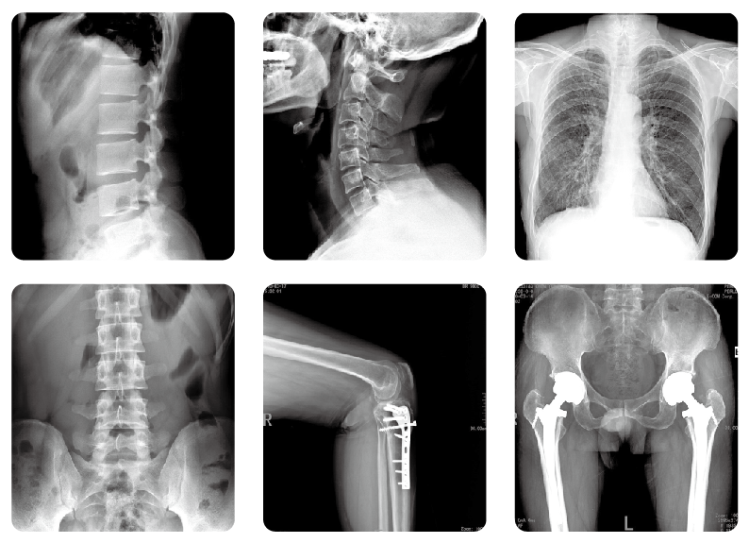

现在我国科技发展速度迅速,人们对于自己身体的健康逐渐重视,很多的医疗设备以及医疗方式逐渐被大众接受。但很多人对医疗方式还是没有太多的了解,就比如放射数字DR、CT检查。进行放射检查的场所大家都看过,上面会有明显的辐射字样,一提到辐射人们就会想到对人体有多大危害,而拒绝进行放射数字DR或CT检查。

放射数字DRhttp://www.pl999.com/newsinfor.php?id=25799&newsclass=1、CT检查所产生的辐射,身体是可以接受的,并不会产生太大的影响,有些患者在进行完检查后,可能任何异常都不会出现。有一部分患者在进行局部CT检查后,有可能会出现头晕呕吐的现象,这一般是由于进行CT检查前,提前注射了对比剂导致的,为的是能够让造影效果更加明显。